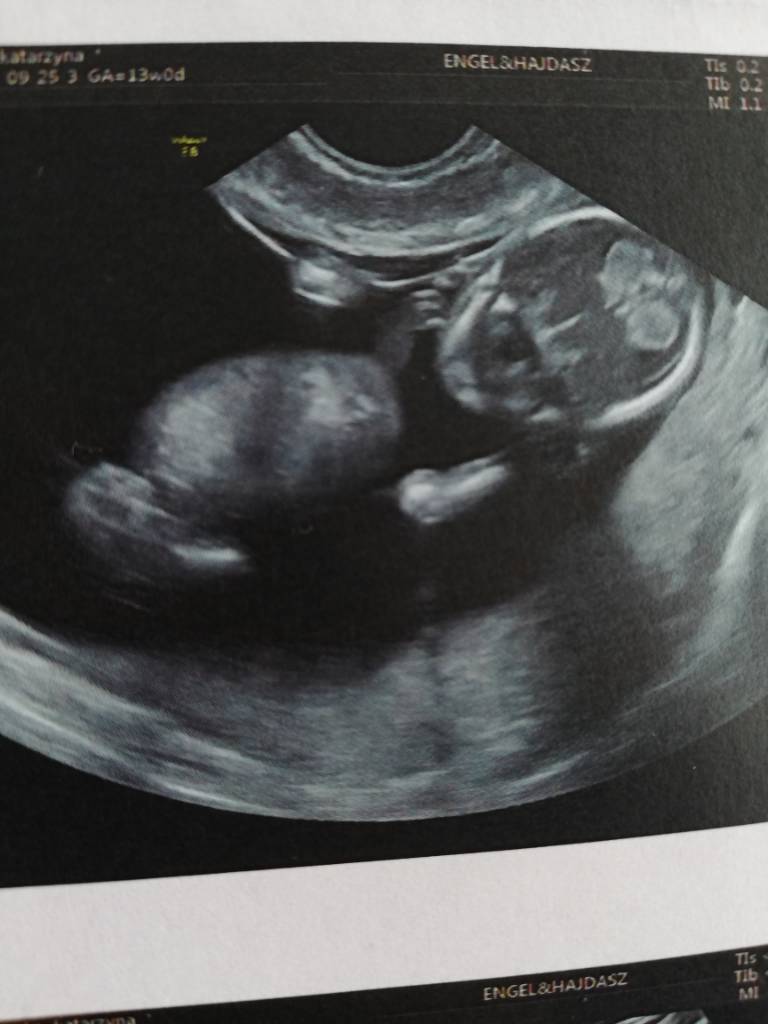

Cudne zdjęciaJa wczoraj byłam na prenatalnych ale po wizycie żeby uczcić poszłam na zakupy a wieoeczorem szybko padlam więc dzisiaj pisze dopieroDzidziuś ma już 6,61 cm tydzień ciąży identyczny jak z usg 13+0. Termin na 02.04. Wszystkie wymiary idealne, pięknie fikal dzidziuś

Wstępnie dr obstawia dziewczynkę ale jeszcze mamy się nie nastawiac. Trochę szok dla mnie bo byłam pewna że będzie drugi chłopczyk. Zobacz załącznik 901859Zobacz załącznik 901860Zobacz załącznik 901861Zobacz załącznik 901863